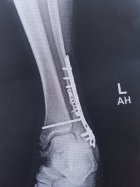

Had my hip replacement performed may 1st. Diagnosed at age 6 with Leg Perthes disease. It kills the ball part of your hip. At age 53 I'd had enough, decided it was time. I was 2 inches short in the left leg. The new hip didn't hurt too bad. The stretching of all my muscles and tendons was/is BRUTAL! Just now getting around semi decent. Lost 30 lbs in the 1st 2.5 weeks, couldn't eat anything without throwing it back up. Had me on 22 pills per day. Once I stopped them I could eat. Then, the muscle relaxer I was on started making me shake in my hands extremely bad. Plus, it made me where I couldn't talk without getting lost in the conversation, I would just lock up. Finally got off of the relaxer, it all went away. It's been a BAD deal, I was regretting it up until about 2.5 weeks ago, just started feeling better 1 day, going pretty decent since then. The picture of my ankle is from 2016, compound fracture. Same leg as my bad hip. Had about 7-8 inches of bone coming out of my leg. Wouldn't recommend. Anyway, heal up fast all you that have had something worked on, I know what you're going through. Screenshot_20240506_165445_File Viewer.jpgResized952016102095151923001.jpg20161130_152428.jpg